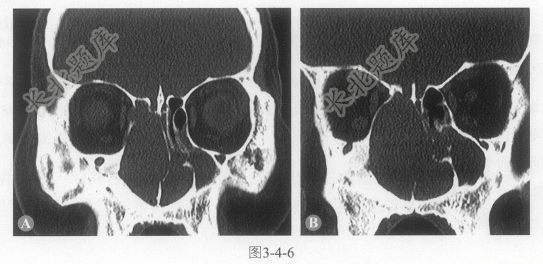

- 单项选择题2.鼻窦CT检查如图3-4-6。下列哪项征象的描述是错误的:

A、双侧鼻腔内见不规则软组织密度影

B、肿物主要位于右侧筛窦鼻腔内,破坏鼻中隔侵入左侧鼻腔

C、膨胀性生长,周围骨壁受压变薄,没有骨质破坏

D、筛顶筛板骨质侵入颅内

E、筛窦外侧壁破坏,肿物侵入眼眶